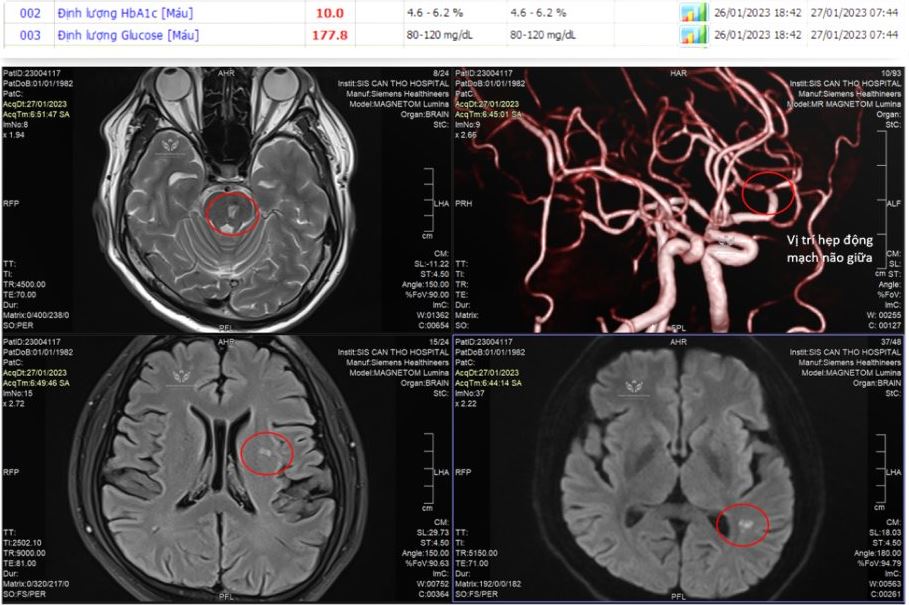

TS.BS Trần Chí Cường – Giám đốc Bệnh viện Đột quỵ Tim mạch Cần Thơ ghi nhận ngày đầu năm mới khám những ca đầu tiên với nỗi lo đột quỵ trẻ trong cộng đồng đang ngày càng phổ biến.

TS.BS Trần Chí Cường – Giám đốc Bệnh viện Đột quỵ Tim mạch Cần Thơ ghi nhận ca trực đầu năm Quý Mão, đã cấp cứu nhiều trường hợp ấn tượng.